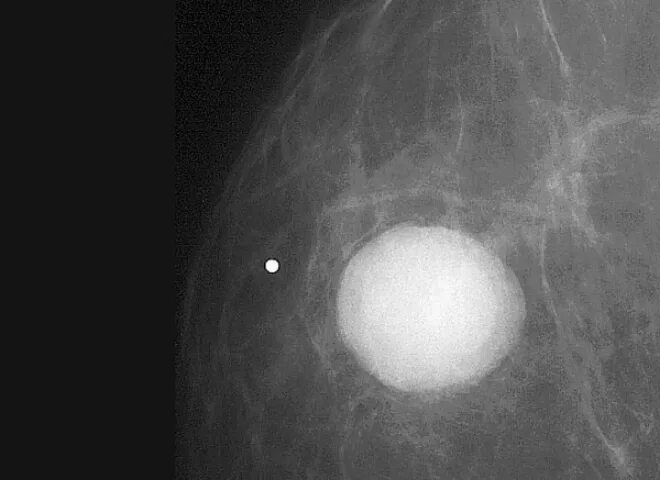

Как выглядит киста молочных желез